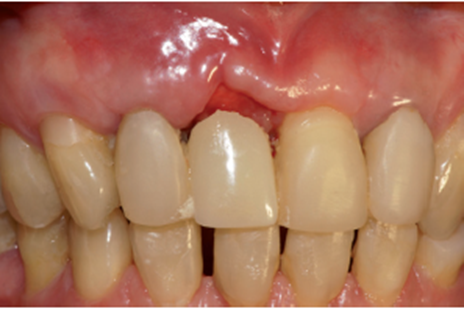

Após quatro meses foi realizado o segundo tempo cirúrgico com fresa cilíndrica diamantada, acessando somente o Cover Screw (Figura 22). O Cover Screw foi removido com a chave de 1.2 (Figura 23), um cicatrizador foi instalado (Figura 24) e o provisório foi reposicionado.